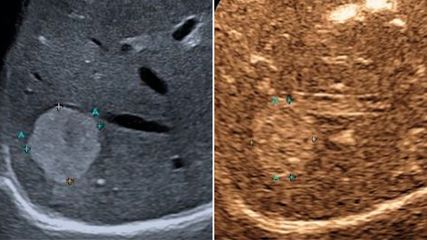

Tatsächlich lagen seine Laborwerte nach vier Monate unter Therapie wieder im grünen Bereich. Es verbesserten sich aber nicht nur die Glukose- und Lipidwerte: Auch die Leberenzyme normalisierten sich. Zudem zeigte die Leberelastografie mittels Fibroscan nun 7,0kPa an, wo vorher noch ein Wert von 11,0kPa erreicht wurde.

Sonografie der Leber – aktuelle Entwicklungen, quantitative Verfahren und klinische Bedeutung

Der vorliegende Übersichtsartikel fasst aktuelle technische Entwicklungen sowie klinische Anwendungen und Limitationen der Lebersonografie zusammen und diskutiert deren Stellenwert im ...